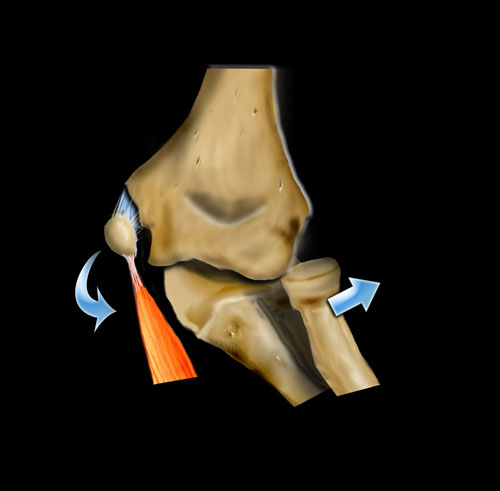

Cơ chế gãy xương quan trọng khác là tình trạng valgus cùi chỏ quá mức.

Khuỷu tay bình thường đã có tư thế valgus sẵn.

Khi trẻ ngã chống tay với cánh tay duỗi thẳng, điều này có thể dẫn đến valgus quá mức.

Ở phía ngoài, điều này có thể dẫn đến trật khớp hoặc gãy xương quay có hoặc không kèm theo tổn thương mỏm khuỷu.

Khi lực tác động nhiều hơn lên xương cánh tay, tình trạng valgus quá mức sẽ dẫn đến gãy lồi cầu ngoài.

Ở phía trong, lực valgus có thể dẫn đến bong lồi cầu trong.

Đôi khi lồi cầu trong bị kẹt trong khớp.

Do tư thế valgus của khuỷu tay bình thường, bong lồi cầu ngoài sẽ ít gặp hơn.